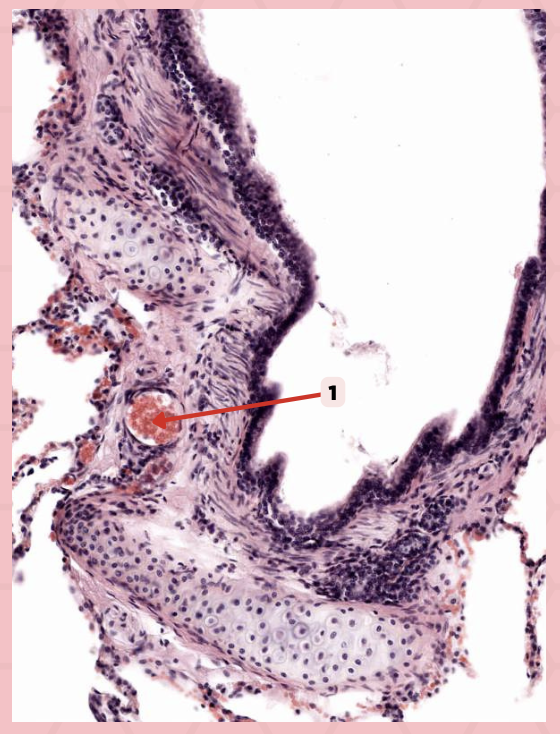

Type 1 and Type 2 Alveolar Cells

What are the 2 cell types for alveoli?

Simple squamous epithelium

What kind of epithelium are these alveolar cells?

Interalveolar septum

Identify the structure labeled as 1.

Type I alveolar cell

Identify the structure labeled as 2.

Type II alveolar cell

Identify the structure labeled as 3.

Pulmonary Alveolar Macrophages (Dust Cells)

Identify the structure labeled as 4.

Pulmonary Alveolar Macrophages (Dust Cells)

What are the most numerous cells inside the alveoli?

Pneumocyte Type I

Which of the following labeled structures covers 95% of the alveolar surface?

Type I alveolar cell

Identify the structure labeled as 1.

Type II alveolar cell

Identify the structure labeled as 2.

Pulmonary Alveolar Macrophages (Dust Cells)

Identify the structure labeled as 3.

Endothelial Cells

Identify the structure labeled as 4.

Visceral Pleura

What type of pleura is a thin layer of connective tissues that borders on the outside by mesothelium?

Simple Squamous Epithelium

What epithelium lines the red arrow?

Mesothelium

Identify the structure labeled as 1.

Pulmonary Capillaries

Oxygenated blood is collected by structure #2 from what source/structure?

Pulmonary Trunk

From what other structure does structure #1 arise from?